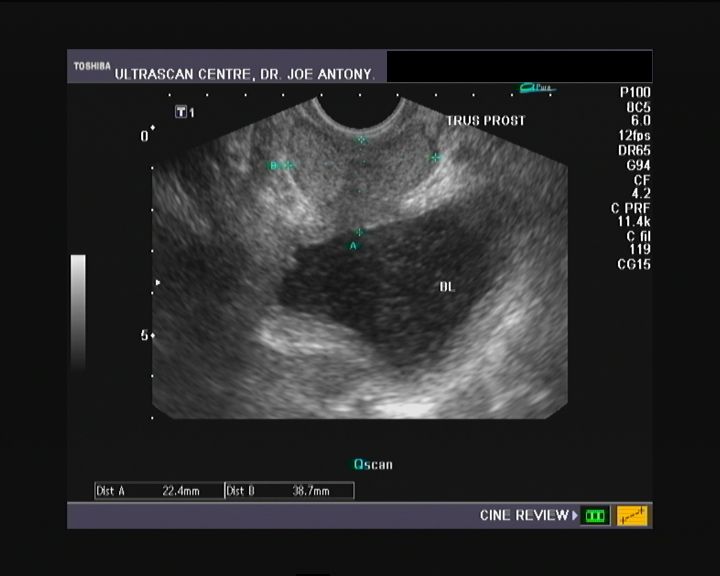

Bladder debris on renal and bladder ultrasound A significant predictor of positive urine What Does Debris In Kidney Mean You can usually treat mild dehydration by increasing fluid and electrolyte. A burning feeling when you urinate. Healthy urine may contain invisible amounts of sediment. For most, the telltale sign is the sudden onset of. Dehydration also places you more at risk of kidney stones, which can cause sediment in the urine. There are quite a few reasons a person. What Does Debris In Kidney Mean.